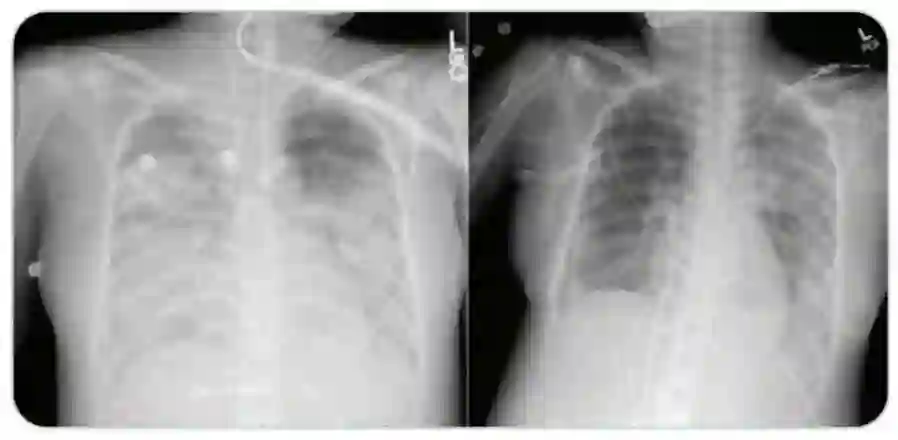

该患者在接受瑞德西韦(Remdesivir)治疗后,患者病情好转,需要的呼吸机支持明显减少,血氧水平和胸部CT检查结果好转。在入院治疗十四天后,已经可以撤离机械通气。 目前患者已出院,正在在家中康复。